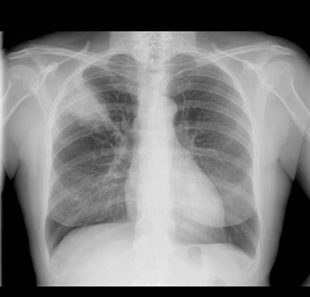

La fracture de côte est très handicapante. La douleur qui s’y associe est(...) Toutes les définitions santé, symptômes et traitements sont sur docteurclic.